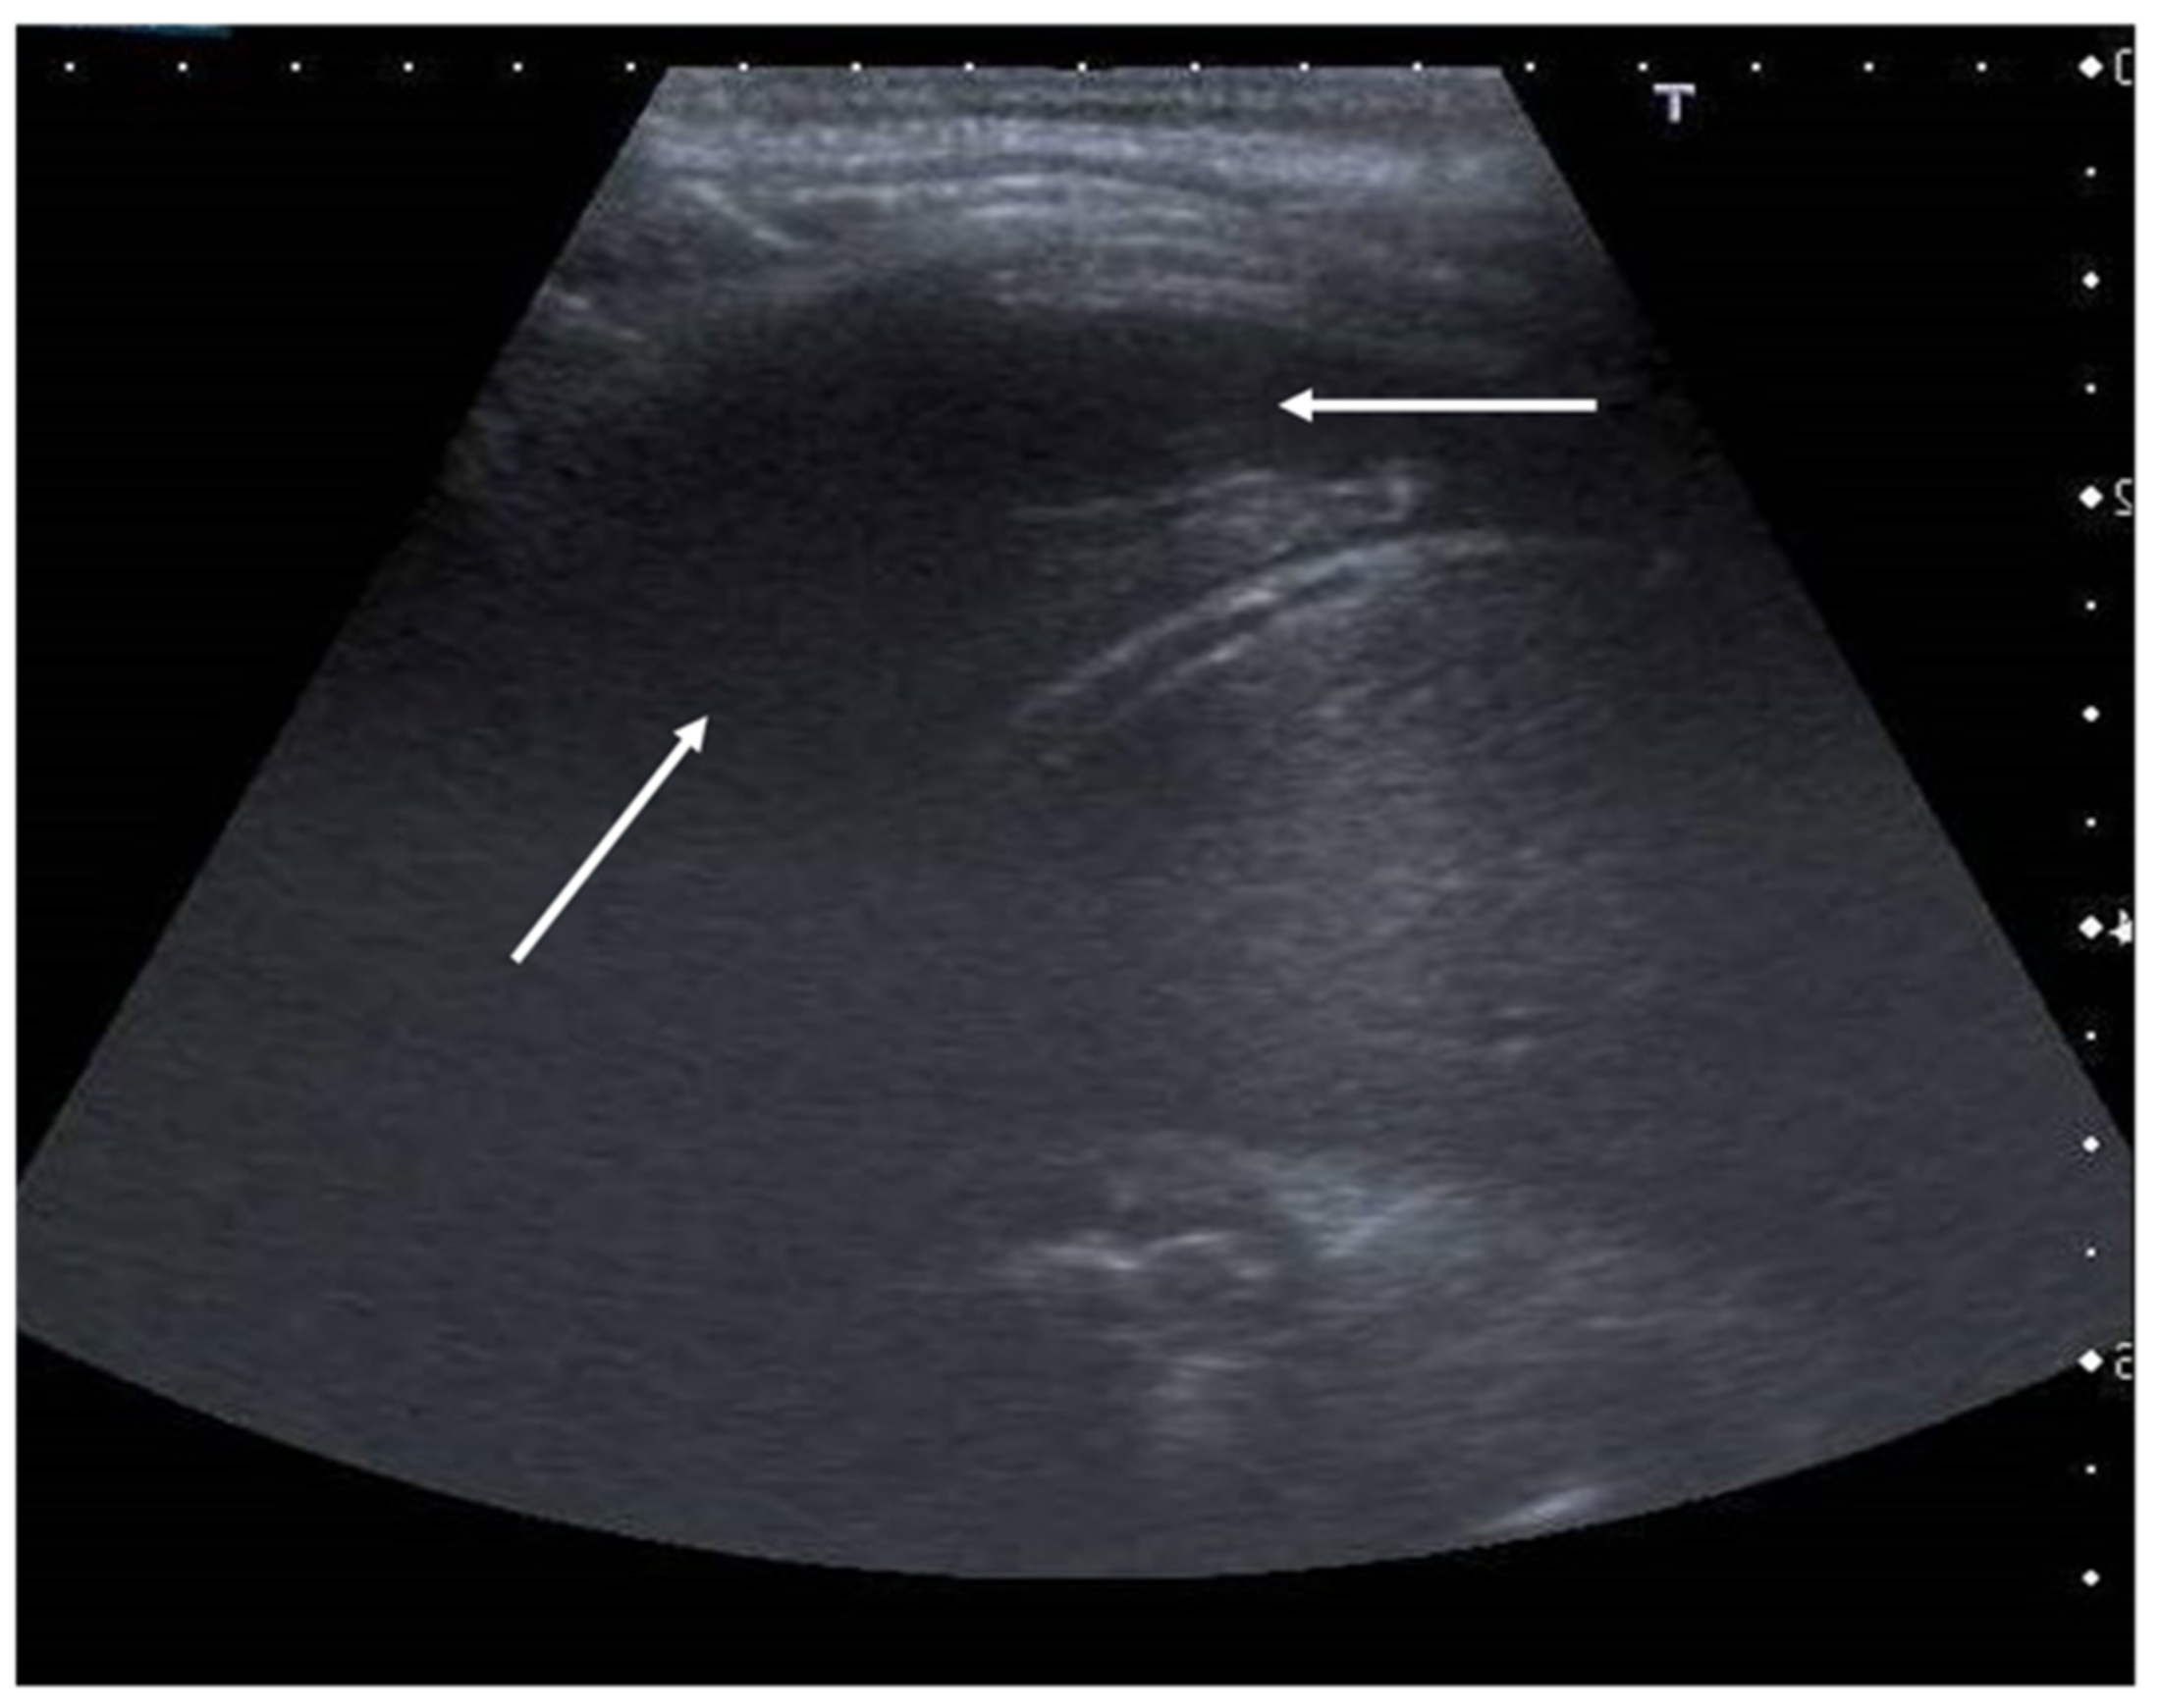

“A-lines” represent some of these artifacts that can be found in a completely healthy lung (Figure 1) [14]. They are horizontal echogenic lines equidistant and parallel to each other and the pleura, representing reverberations of the pleura itself that arise when the ultrasound beam reflects off of the pleura and partially reflects off of the probe face back to the pleura again before getting back to the machine instead of entering the probe. They are caused by the large difference in acoustic impedance between the pleura and the air contained in the lungs. The distance from each other is related to the distance between the pleural line and the skin surface, and their position does not change with respiratory acts.

Figure 1. Appearance of a healthy lung. White arrows show pleural and A-lines.